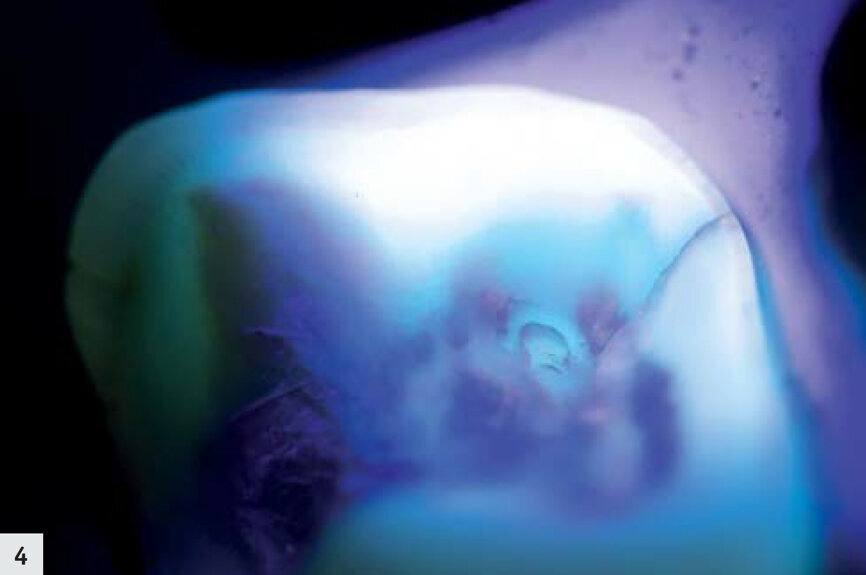

Figs. 4–5 : On peut observer une fissure très fine dont l’aspect est légèrement sombre ; aucune activité bactérienne n’est visible.

Les deux cas présentés par la suite illustrent comment le mode détection se révèle utile dans le cadre de votre pratique quotidienne. Un patient s’est présenté avec une ancienne restauration à l’amalgame défectueuse (Fig. 1). Après l’élimination de l’amalgame, des produits résultant de la corrosion et une fissure présente jusque dans la dentine ont été détectés dans la zone mésio-linguale ; l’aspect de la dentine environnante était légèrement plus sombre (Figs. 2–3). Sous le rayonnement proche-UV du mode détection, elle est apparue sous la forme d’une très fine ligne violette, due à la diffraction de la lumière au niveau de la fissure ; toutefois, la dentine environnante s’est révélée saine et sans métabolites bactériens, dans la mesure où aucune fluorescence rouge-orangée n’était observée (Figs. 4–5). Les cuspides ont été réduites afin de minimiser le risque d’une propagation de la fissure, mais aucune préparation supplémentaire n’a été nécessaire.